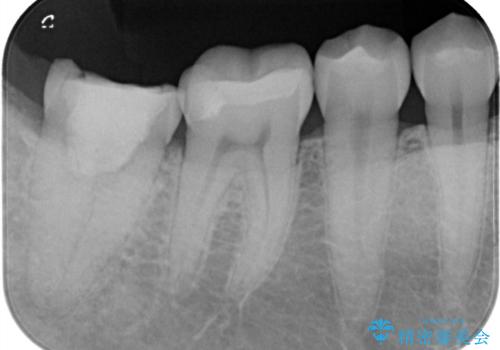

セラミックインレーの術後

金属は真っ白に写ってしまうため、2次虫歯の有無が分かりにくいことが欠点の一つです。セラミック(ジルコニア以外)は、レントゲン写真において、実際のご自身のエナメル質と同じくらいの濃淡で写ります。そのため、定期的なメンテナンスの際に、虫歯が内部で広がっていないかのチェックをすることが可能です。